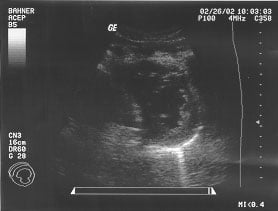

Cardiac - Subxiphoid view (unlabeled)

Cardiac - Subxiphoid view (labeled)